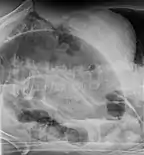

Coffee bean sign in a person with sigmoid volvulus Coffee bean sign in a person with sigmoid volvulus

.jpg.webp) CT scan of a small bowel volvulus. It shows two juxtaposed segments of narrowing, which is the spot of mesentery rotation. The other signs indicate strangulation. CT scan of a small bowel volvulus. It shows two juxtaposed segments of narrowing, which is the spot of mesentery rotation. The other signs indicate strangulation.